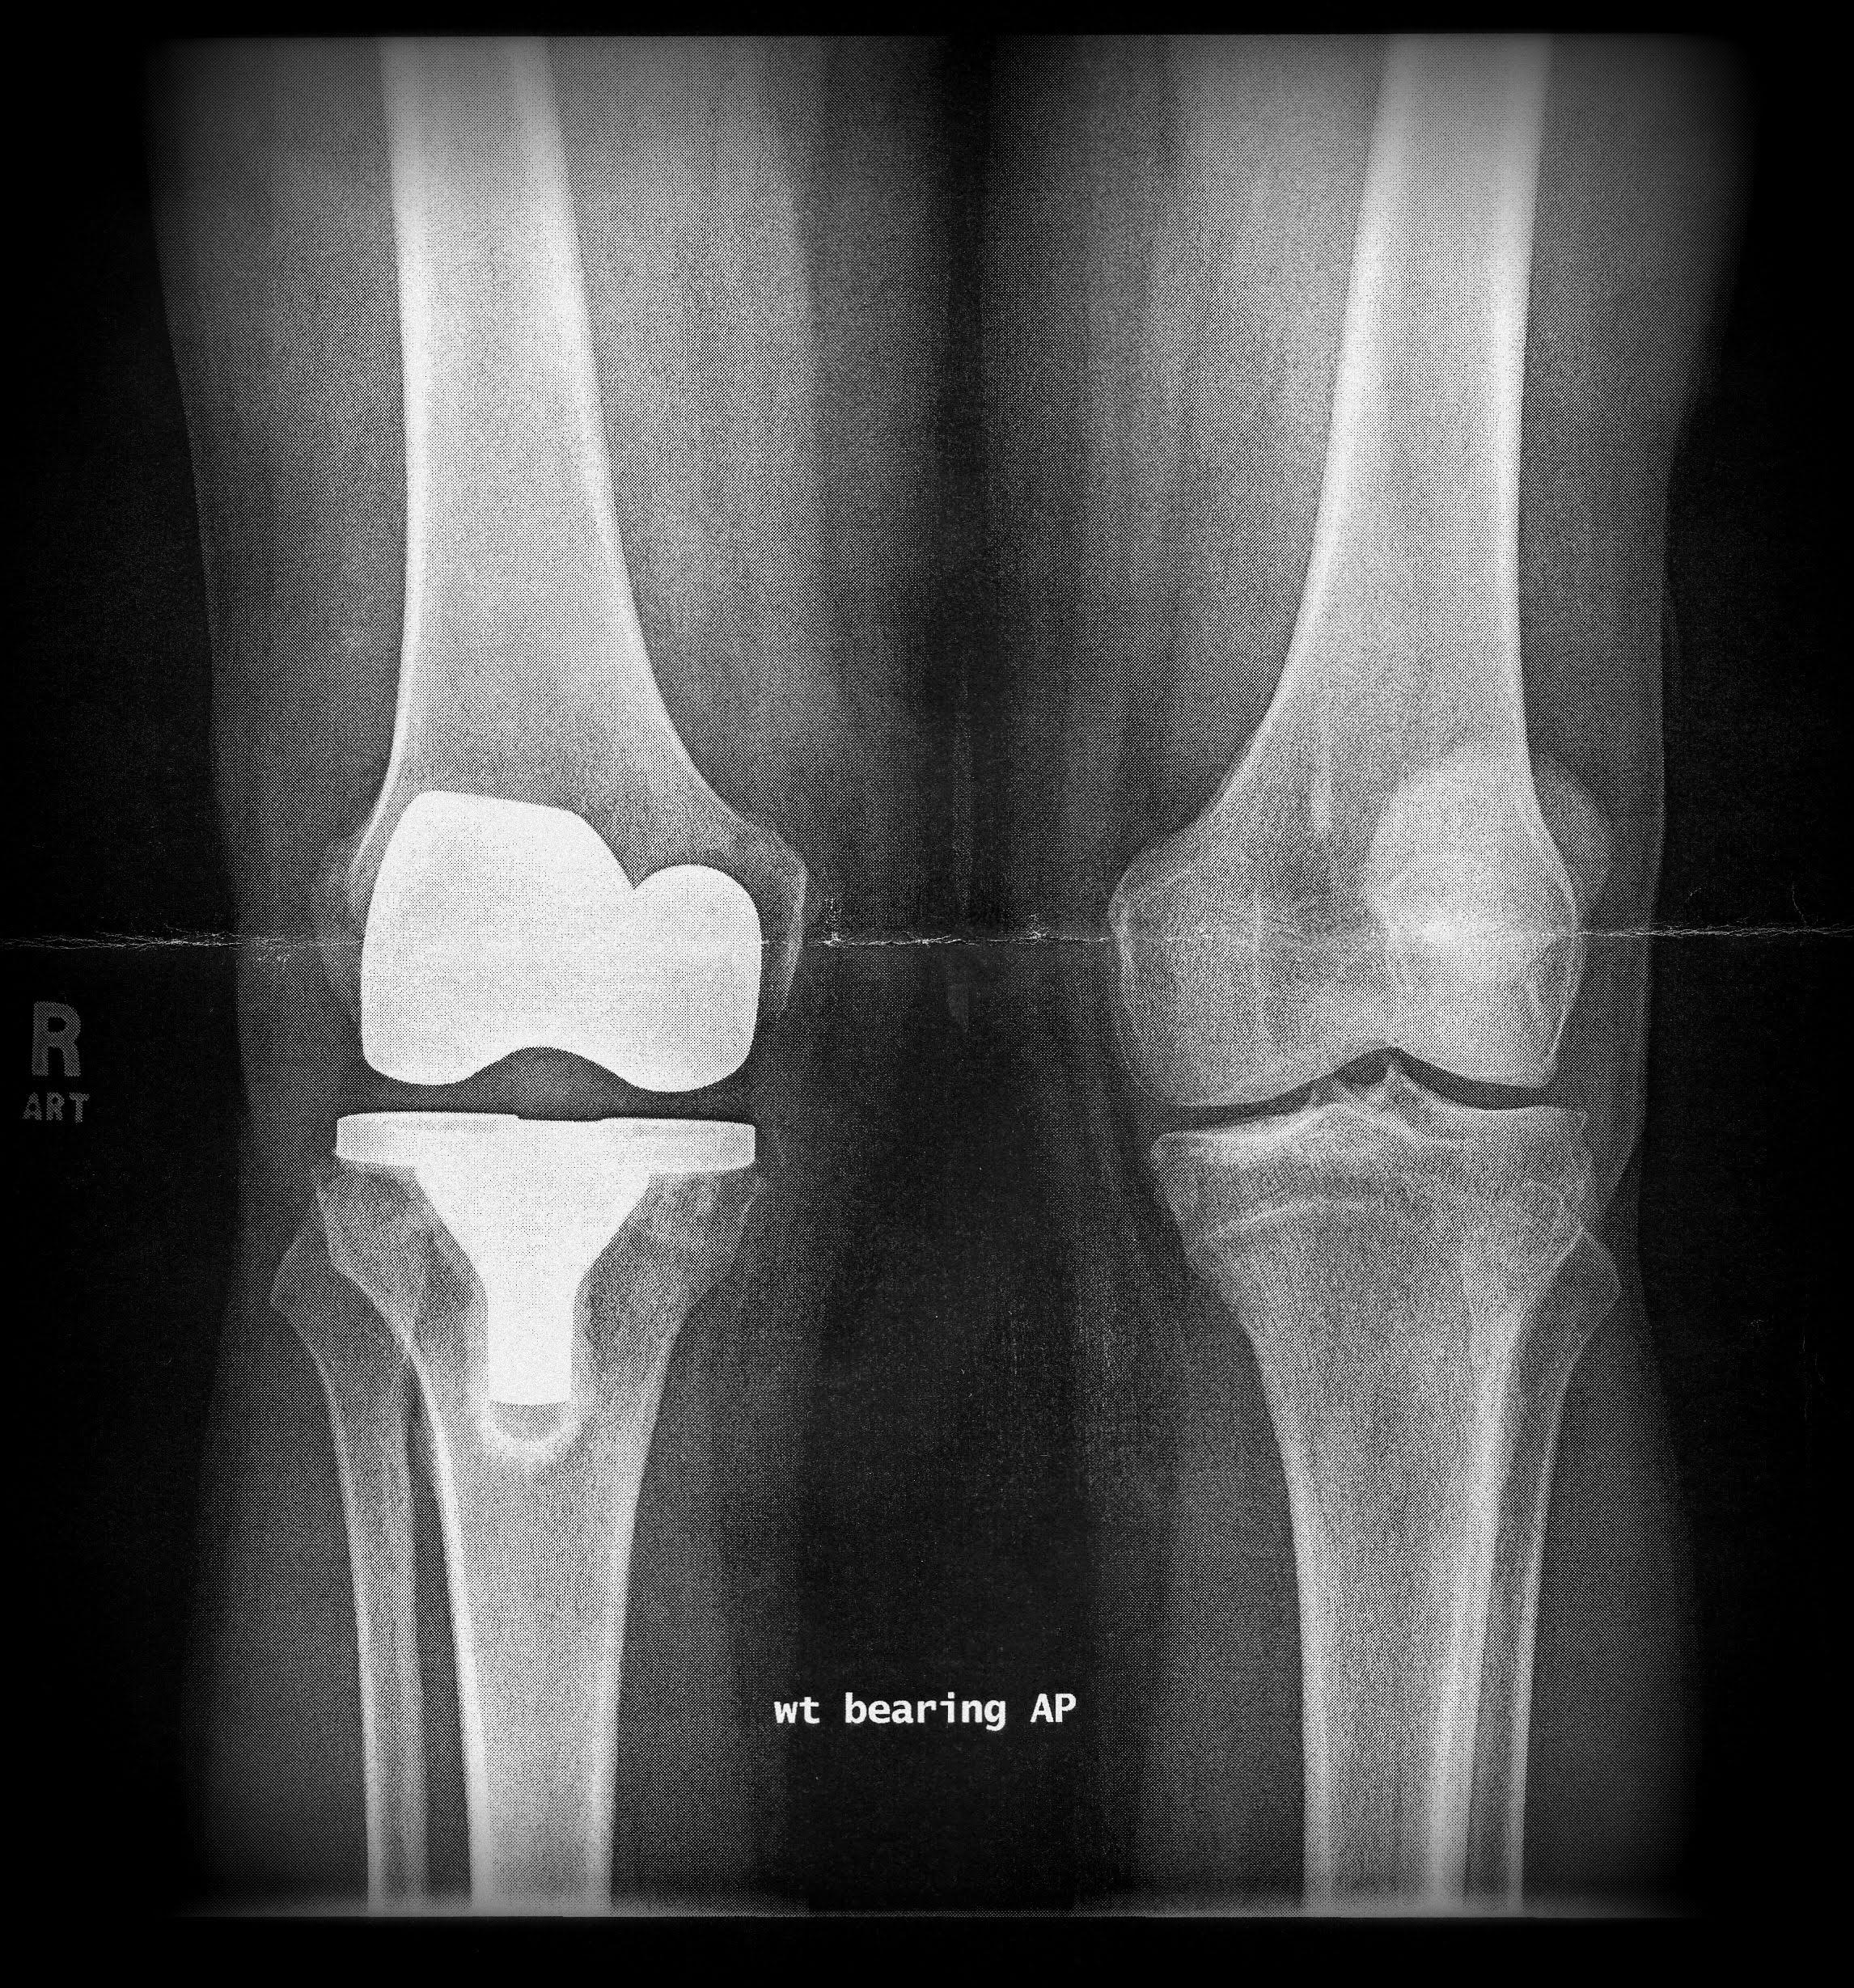

X-ray technology is used to examine many parts of the body.

Bones

- Fractures and infections. In most cases, fractures and infections in bones and teeth show up clearly on X-rays.

- Arthritis. X-rays of your joints can reveal evidence of arthritis. X-rays taken over the years can help your doctor determine if your arthritis is worsening.

- Osteoporosis. Special types of X-ray tests can measure the density of your bones.

- Bone cancer. X-rays can also reveal tumors in your bones.